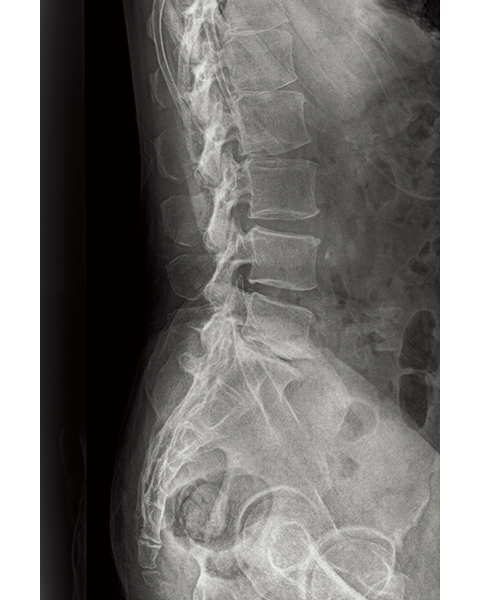

Multiple body parts supported

Lumber Spine